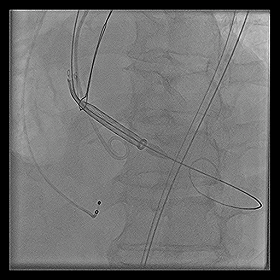

◆2015年1月17日行TAVI术。

◆植入29mm CoreValve人工支架瓣膜一枚。

术后症状明显缓解,近一年未因心衰住院;

一年期复查心超,未见主动脉瓣狭窄和关闭不全。